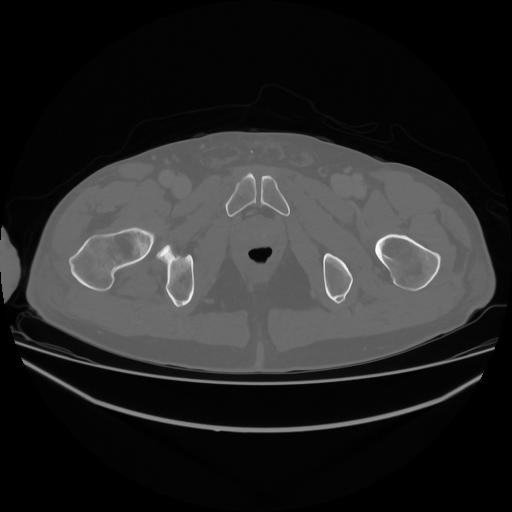

5 CUERPO,CE,Vol,1.0,CUERPO,,